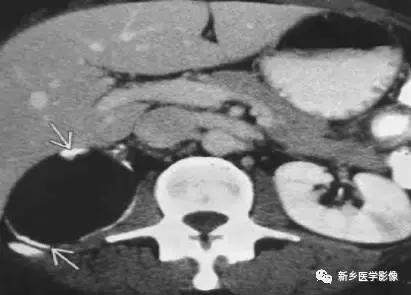

13、肾脏肿瘤

主要包括合并钙化的常见肿瘤或肿瘤样病变,如:肾囊肿,肾细胞癌,多房囊性肾瘤,多囊肝多囊肾囊壁钙化,肾脏结核,肾脏钙乳症。